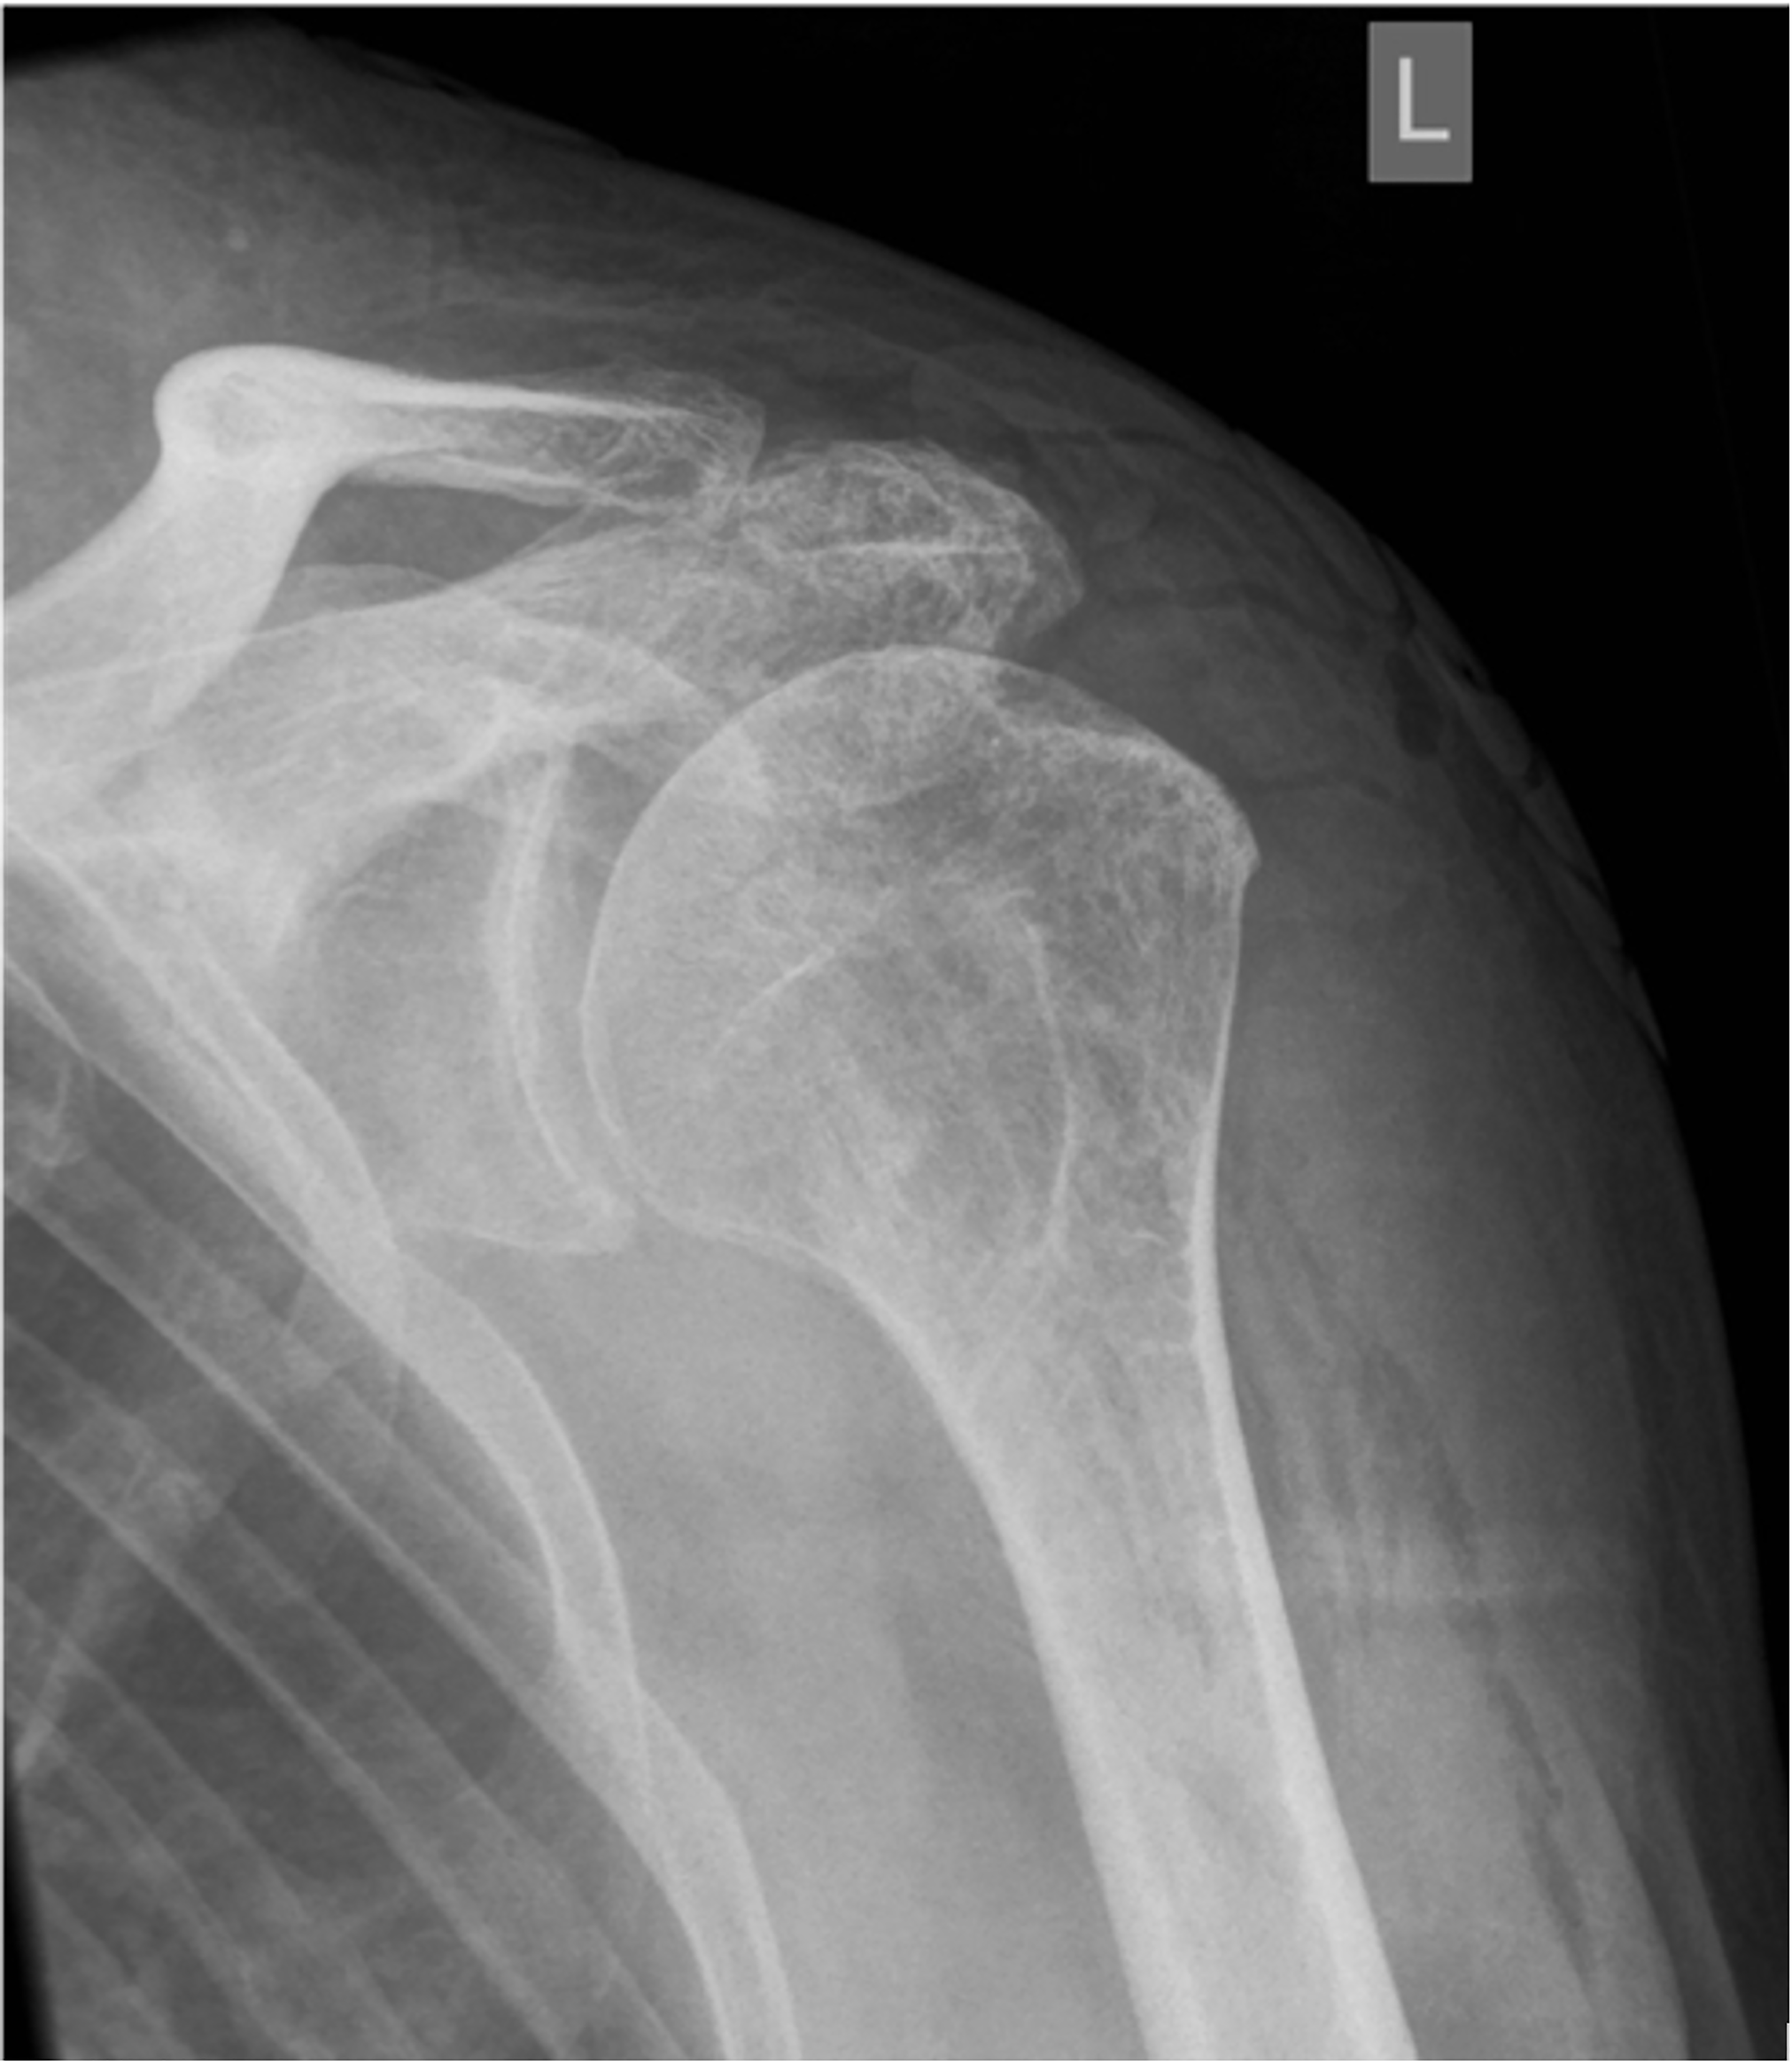

In the future, several properties of the implant effect and outcome of the procedure have to be addressed. It is not clear, why the positive effect of the biodegradable spacer continues beyond the time of its degradation period, which begins at 3 months and dissolves by 12 months (16,29). In this regards, influence of the spacer implantation on the acromiohumeral distance (AHD) is interesting. It was noted that AHD increased immediately after spacer implantation (Figure 3) (11).

However, this effect was not consistent finding on long-term follow up. While Oh reported higher AHD after spacer implantation comparing to other modes of treatment, Deranlot showed that AHD was reduced by 2,1 mm comparing to preoperative value (18,27). Even more interesting was observation of Familiari that higher postoperative AHD was predictive of a lower Constant score at final follow-up (29). This seems not to be logical because the spacer is designed to restore a more normal AHD to allow a more normal shoulder kinematics. It seems that after a certain point, greater AHD may actually interfere with shoulder mechanics. Additionally, one can suspect that the spacer works more as a biological spacer or cushion between the humerus and acromion rather than by truly restoring more normal shoulder biomechanics.